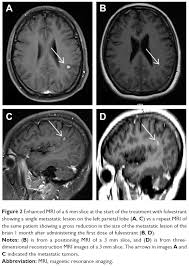

In other cases, the body is able to. Persistent, progressively worsening headaches or pressure to the head There are two types of brain cancer known as primary and metastatic. The symptoms caused by a brain metastasis depend on the tumor's location. The women with brain metastasis, who had not yet developed symptoms at the time the metastases to the brain were discovered survived, on average, 10.4 months. Primary brain cancer occurs when a tumor develops in the brain while metastatic, however, refers to cancer that originated elsewhere in the body and then traveled to the brain. Metastases can push on or cause swelling in specific areas causing specific symptoms. Local therapies for brain metastasis include surgery and different types of radiation therapy. According to the national breast cancer foundation, the symptoms of metastatic breast cancer vary as far as type and severity depending on the site of metastasis (spreading). Symptoms can include sudden weakness or numbness on one side of the body, headache, trouble speaking, vision changes, dizziness and/or loss of balance These are the symptoms to watch for according to where mbc. Learn the signs and symptoms of metastasis, how you can make. The most common symptom of brain metastases is a headache.

Two Cases Of Possible Remission In Metastatic Triple Negative Breast Cancer Mdedge Hematology And Oncology from cdn.mdedge.com If your breast cancer spreads to other parts of your body, doctors will call it metastatic. (metastasize means to spread.) it tends to go to the bones, lungs, liver, and brain.you'll get. The women with brain metastasis, who had not yet developed symptoms at the time the metastases to the brain were discovered survived, on average, 10.4 months. Though symptoms vary from patient to patient, common brain metastasis symptoms include: On the following pages you can read about: Brain metastases are growths that spread to the brain from a cancer in another part of the body. Not everyone with a brain metastasis will have symptoms but most do. Headaches, sometimes with nausea and vomiting. These are often the first symptoms of a brain metastasis.

Symptoms of brain metastases symptoms of brain metastases depend on the location, size and number of growths in the brain, or the amount of swelling. Other signs and symptoms of brain metastases include: Nausea (feeling sick) or vomiting (being sick) can be caused by secondary breast cancer in the brain or elsewhere in the body, its treatment or emotional side effects such as anxiety. Brain metastases are growths that spread to the brain from a cancer in another part of the body. Or, the cause of a symptom may be a different medical condition that is not cancer. However, for about 17% of women in this group, the brain is the only site of metastasis. The symptoms of metastatic breast cancer can be very different depending on the location of the cancer: They are distinct from primary brain tumors, which start in the brain. Signs and symptoms of brain metastases include: Headache, sometimes with vomiting or nausea mental changes, such as increasing memory problems An estimated 150,000 to 200,000 people are diagnosed with a brain metastasis each year, compared to about 17,000 diagnoses for primary. Persistent, progressively worsening headaches or pressure to the head Primary brain cancer occurs when a tumor develops in the brain while metastatic, however, refers to cancer that originated elsewhere in the body and then traveled to the brain.